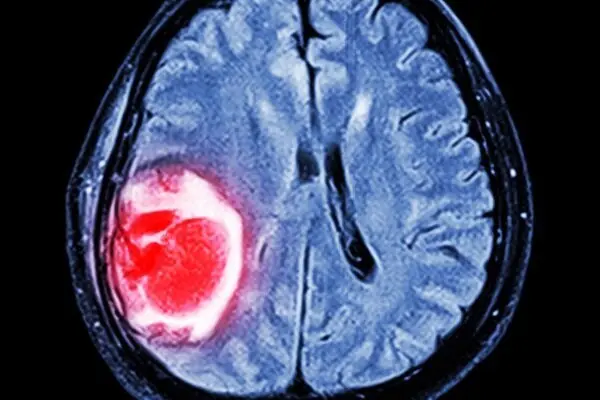

به گزارش سایت دیده بان ایران به نقل از مدیسن نت، تیمی از محققان دانشگاه رن فرانسه میگویند: «این موارد بدخیم شامل سرطانهای مثانه، مغز و دهانه رحم هستند.»

این مطالعه نشان داد که احتمال ابتلاء به هر نوع سرطان در افراد مبتلا به ام اس در مقایسه با افرادی که ام اس ندارند، ۶ درصد بیشتر است. افزایش خطر برای سرطانهای مثانه (۷۱٪)، تومورهای مغزی (۶۸٪) و سرطان دهانه رحم (۲۴٪) بیشتر بود.

لیری توضیح داد: «در حالی که مطالعه ما خطر بالاتری را برای سرطان مغز نشان داد، ممکن است تا حدی به دلیل تشخیص زودهنگام این سرطان در افراد مبتلا به ام اس باشد، زیرا آنها به طور منظم اسکن مغزی انجام میدهند که ممکن است سرطانها را زودتر، قبل از اینکه فرد علائمی داشته باشد، تشخیص دهد.»